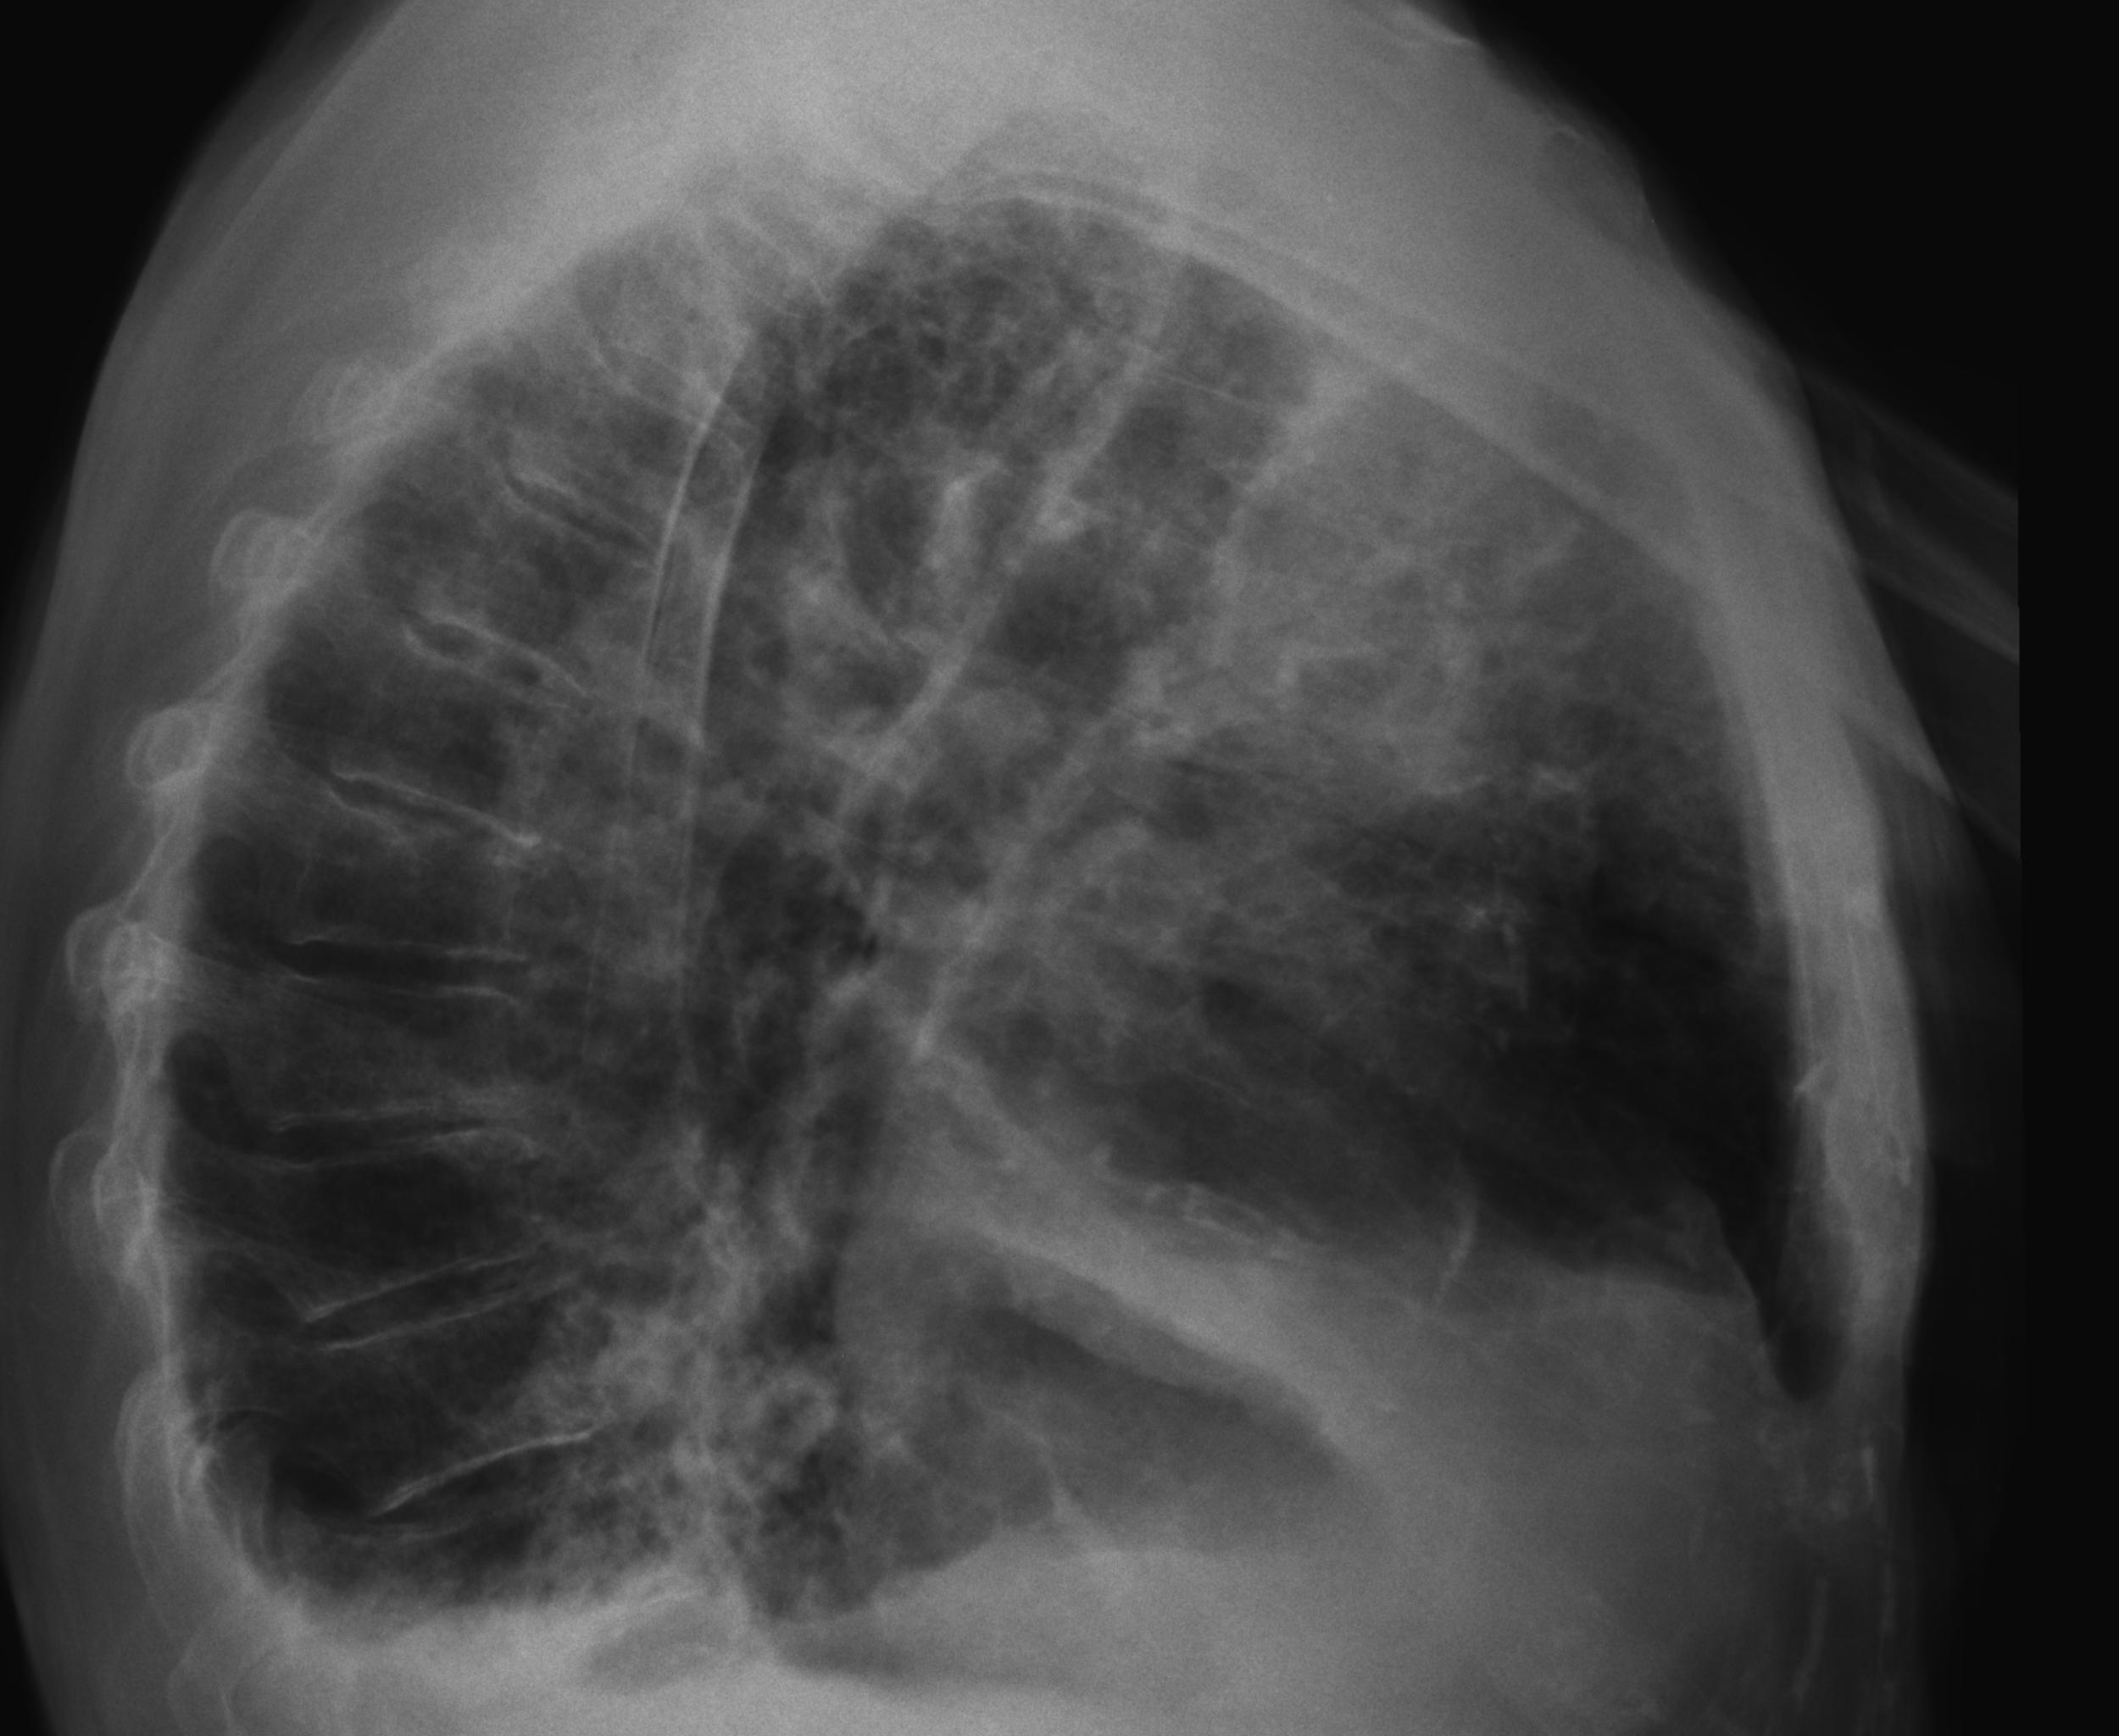

Caso Número 4/2018: “Uma sessão interativa de casos em radiologia torácica – Parte 1”

Caso relatado na Reunião de Discussão de Casos Clínicos do Hospital Universitário Prof. Polydoro Ernani de São Thiago, iniciada pelos Profs. Jorge Dias de Matos, Marisa Helena César Coral e Rosemeri Maurici da Silva, em julho de 2017. No dia 14 de junho de 2018, no auditório do HUPEST, realizou-se a apresentação e discussão do caso cujo registro é apresentado a seguir. Trata-se da discussão de onze casos em radiologia torácia, de forma interativa com a plateia, e assim ocorre também neste artigo.